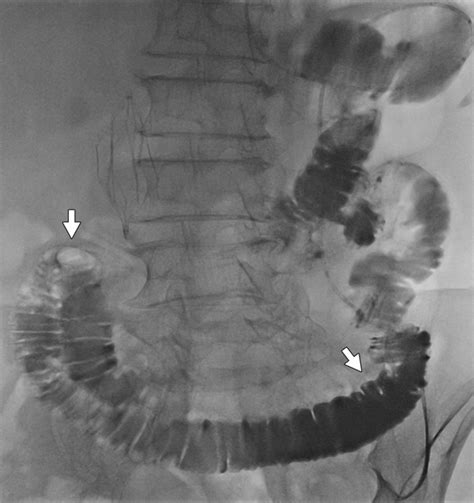

Diagnostic Approaches

Diagnosing this condition requires a combination of clinical suspicion and advanced imaging techniques. Because the symptoms can mimic other gastrointestinal issues, such as gallbladder disease or pancreatitis, accurate diagnostics are essential. Medical professionals typically employ the following methods:

Computed Tomography (CT) Scan Visualizes the distended afferent limb and identifies the site of the obstruction.